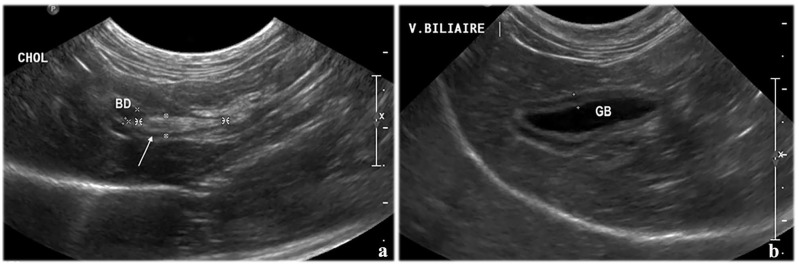

Case summary: A 10-year-old neutered female domestic shorthair cat was presented to our hospital with a 2-day history of anorexia, vomiting and lethargy. The biochemistry panel revealed increased hepatic enzyme activity and serum amyloid A concentration. Haematological values were within reference intervals. An abdominal ultrasound identified a hyperechoic spindle-shaped structure within the common bile duct and a suspected secondary subobstruction, associated with signs of intra- and extrahepatic biliary tract inflammation. During hospitalisation, the cat developed severe and sustained ionised hypercalcaemia. Exploratory surgery was elected as a result of the lack of clinical improvement, despite supportive treatment and suspected retrograde migration of the spindle-shaped structure. Two grass awns were extracted at the junction of an extrahepatic duct and the common bile duct via choledochotomy using intraoperative ultrasound guidance. A stent was then placed in the bile duct to prevent subsequent bile leakage. Histopathology of the liver revealed a moderate neutrophilic and lymphoplasmacytic inflammation with rare bacterial colonies. Escherichia coli was cultured from a bile sample. No specific cause of hypercalcaemia was identified. The cat recovered uneventfully from surgery. Hepatic enzyme activities and hypercalcaemia progressively decreased within a few weeks after surgery and remained within the reference intervals without treatment. Therefore, hypercalcaemia was suspected to be secondary to a foreign body-related granulomatous reaction.

Relevance and novel information: To our knowledge, only one other feline case report of biliary tract obstruction secondary to a biliary foreign body has been described in the literature. This is also the first case reporting the use of intraoperative ultrasound to localise a vegetal foreign body within the biliary tract of a cat. This case is also unique because of the onset of hypercalcaemia suspected to be secondary to a foreign body-related granulomatous reaction.